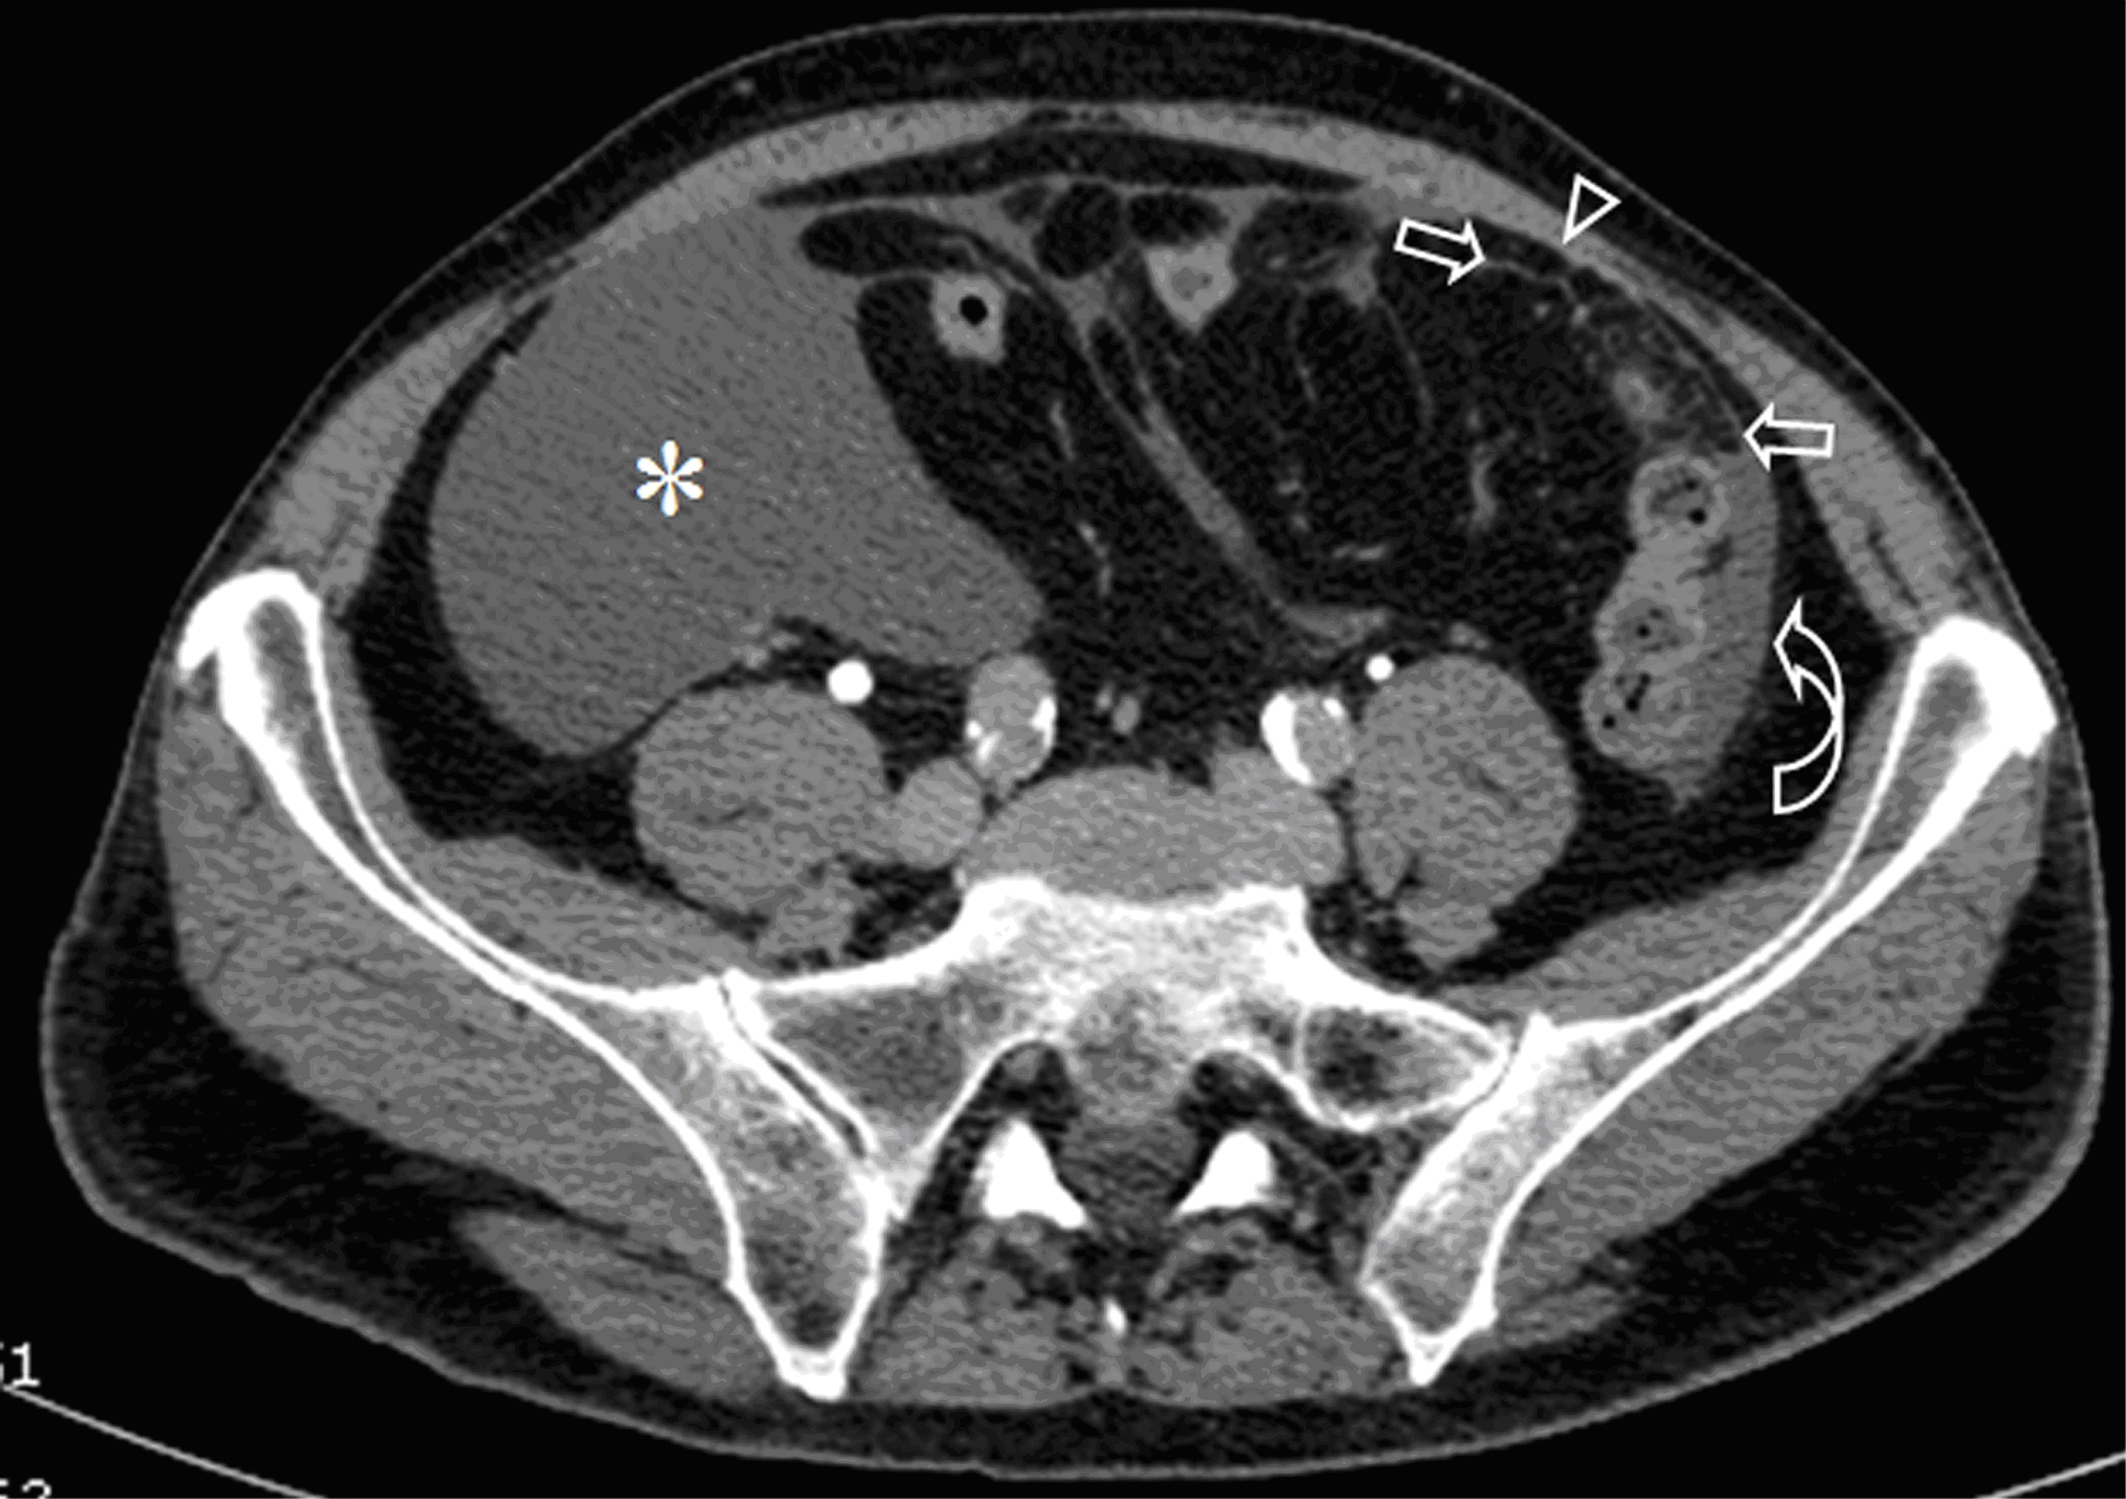

Peritoneal mesothelioma causes, stages, and treatment. Peritoneal mesothelioma has a long latency period. Several decades long, this is the time between exposure to asbestos and diagnosis of cancer. Though the asbestos fibers begin to do damage as soon as they enter the body, it takes many years for their impact to be felt and noticed. Vegetarian and vegan diets for cancer mesothelioma. A healthier diet for mesothelioma and cancer patients. All the reasons vegan and vegetarian diets reduce cancer risks, also make them good for cancer patients. What is mesothelioma and types of mesothelioma mesothelium info. Mesothelioma cancer develops from the linings of specific spaces or organs in the body, called the mesothelium. There are four key kinds of mesothelioma, such as malignant pleural mesothelioma, peritoneal mesothelioma, pericardial mesothelioma, and esophageal disease. Pleural mesothelioma entails tumors inside the pleura (lung linings). Stages of peritoneal mesothelioma early stage vs. Advanced. Quick summary. Peritoneal mesothelioma is an exceedingly rare diagnosis, with only around 500 new cases per year in the united states. Because it’s so rare and often isn’t diagnosed until it has reached significant metastasis (spreading), it’s difficult for specialists at this time to form an official peritoneal mesothelioma staging system. Peritoneal mesothelioma causes, treatment & survival rates. Peritoneal mesothelioma is a cancer that forms in the tissue lining of the abdomen (peritoneum). It is caused by ingesting asbestos. It is the secondmost common type of mesothelioma. Half of patients who elect surgery with heated chemotherapy live at least five years. Peritoneal mesothelioma is a. Peritoneal mesothelioma a review pubmed central (pmc). Peritoneal mesothelioma was first described in 1908 by miller and wynn. It is a rare neoplasm with a rapid fatal course (median survival 612 months, mean symptomstosurvival time 345 days). In the united states, the overall prevalence is 12 cases per million, with an estimated incidence of 200400 new cases annually.

The 4 mesothelioma stages & staging systems involved in diagnosis. Peritoneal mesothelioma staging. There is no accepted system for staging peritoneal mesothelioma. This type of mesothelioma is clinically defined by whether it is localized or metastatic. However, doctors may label peritoneal mesothelioma with a stage they feel is appropriate based on how much the cancer has metastasized. Peritoneal mesothelioma causes, treatment & survival rates. Peritoneal mesothelioma is a cancer that forms in the tissue lining of the abdomen (peritoneum). It is caused by ingesting asbestos. It is the secondmost common type of mesothelioma. Half of patients who elect surgery with heated chemotherapy live at least five years. Peritoneal mesothelioma is a. How is mesothelioma diagnosed? Mesolawyerscare. Mesothelioma is a difficult diagnosis to make. The symptoms as presented are also symptoms of many more common diseases. Malignant mesothelioma makes up less than 1% of all the cancers diagnosed annually in the united states. To be given a diagnosis of malignant mesothelioma is most commonly done after extensive testing and elimination of other []. Lumicell inc.. For surgeons. Lumicell is changing the landscape of cancer surgery with a handheld imaging system that enables surgeons to identify any cancer cells left behind on the tumor cavity walls and take action in realtime to improve patient outcomes. Mesothelioma prognosis life expectancy & survival rates. The prognosis for mesothelioma is poor, but there are some ways to increase your life expectancy. Discover survival rates, recurrence and remission rates and more statistics at maa center. Peritoneal mesothelioma. The tumor is also very fast growing. The combination of late diagnosis and rapid growth rate combine to make peritoneal mesothelioma a very deadly disease. In fact, up until ten years ago, peritoneal mesothelioma was considered universally fatal. Even with aggressive treatment, most people with peritoneal mesothelioma will die from the disease. Effusion definition of effusion by medical dictionary. Effusion [ĕfu´zhun] 1. Escape of a fluid into a part; exudation or transudation. 2. An exudate or transudate. Chyliform effusion see chylothorax. Chylous effusion see chylothorax. Pericardial effusion the accumulation of an abnormally large amount of pericardial fluid in the pericardium. Accumulated fluid from a pericardial effusion evacuated by the.